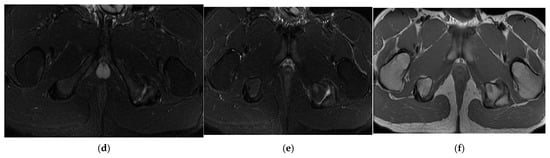

3.2. Case 2: Proximal Hamstring Avulsion with Sciatic Neuritis

In the second case, the patient, a left back, experienced pain in the inguinal region and left thigh while running during a national team training session. This 23-year-old national team member has six years of experience as a first-league professional in Romania, standing 202 cm tall and weighing 105 kg. Pelvic radiography was incorrectly performed (incorrectly) and the patient was diagnosed with left thigh muscle damage. (Figure 4).

Three years post-trauma, the player develops symptoms of peripheral neuropathy with sensory and motor symptoms in the external popliteal sciatic nerve. Lumbar degenerative disc disorder or piriformis syndrome was suspected, and lumbar and pelvic MRI was performed.

The spinal MRI revealed no evidence of degenerative lumbar disc pathology or radiculopathy (Figure 5). Magnetic resonance imaging (MRI) and radiographic examination of the pelvis revealed an old avulsion injury with a detached bone fragment at the insertion site on the left ischial tuberosity, involving the semitendinosus, semimembranosus, and biceps femoris muscles (collectively referred to as the ischium-calf muscles). This condition has led to the development of pseudoarthrosis and bone edema at the level of the ischial tuberosity. The sciatic nerve is positioned tangentially to the inflammatory response. Despite the detachment, the bone fragment remains vascularized due to the maintained insertion of the ischial calf muscles, preventing it from becoming a bone splinter (Figure 6 and Figure 7).

Figure 6.

(a) Pelvic MRI: coronal stir acquisition, (b) pelvic MRI: sagittal PD fat sat acquisition, (c) pelvic MRI: sagittal PD fat sat acquisition, (d) axial stir acquisition, (e) axial stir acquisition, (f) axial T1 acquisition.

The pseudoarthritis secondary to the old ischial tuberosity avulsion can be visualized as follows:

- -

- An old detached bone fragment with signal in the T1 and T2 ponderations, similar to the rest of the existing bone structures, but showing focal alterations of the PD fat sac and STIR hypersignal, indicating bone edema.

- Fluid accumulation in T2 hypersignal, T1 hyposignal, between the torn bone fragment and the remaining tuberosity

- The altered PD fat sac hypersignal in the sciatic nerve, adjacent to the inflammatory process, indicates changes suggestive of focal neuritis.

Surgery might be applied either for the surgical treatment of pseudoarthritis or the excision of the detached fragment with reinsertion of the ischial–calf muscles, both treatment variants were refused by the patients due to long-term postoperative recuperation, as the player was training for international competitions.

Treatment eventually consisted of rest and NSAIDs; the inflammatory process decreased in size and, consequently, contact with the sciatic nerve. The radicular phenomena progressively decreased until complete remission was achieved and returned to play after 3 weeks.